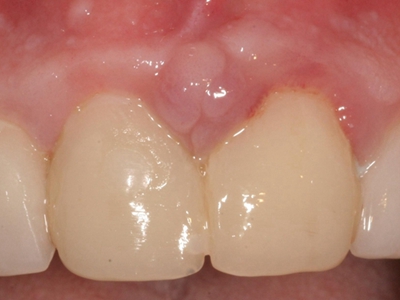

牙龈瘤是指发生在龈乳头部位的炎症反应性瘤样增生物,好发于女性,前磨牙区最为常见。牙龈瘤来源于牙周膜及牙龈的结缔组织,因其无肿瘤的生物学特征和结构,故非真性肿瘤,但切除后易复发,因此切除务必彻底,必要时拔除相关牙齿。

牙龈瘤多发于女性,以青年及中年人为常见,多发生于牙龈乳头部,位于唇、颊侧者较舌、腭侧者多,最常见的部位是前磨牙区。肿块较局限,呈圆形或椭圆形,有时呈分叶状,大小不一,直径由几毫米至数厘米。

肿块有的有蒂,如息肉状;有的无蒂,基底宽广,生长较慢,但在女性妊娠期间可能迅速增大。较大的肿块可以遮盖一部分牙及牙槽突,表面可见牙压痕,易被咬伤而发生溃疡,伴发感染。随着肿块的增长,牙槽骨壁逐渐被破坏,牙可能发生松动、移位。